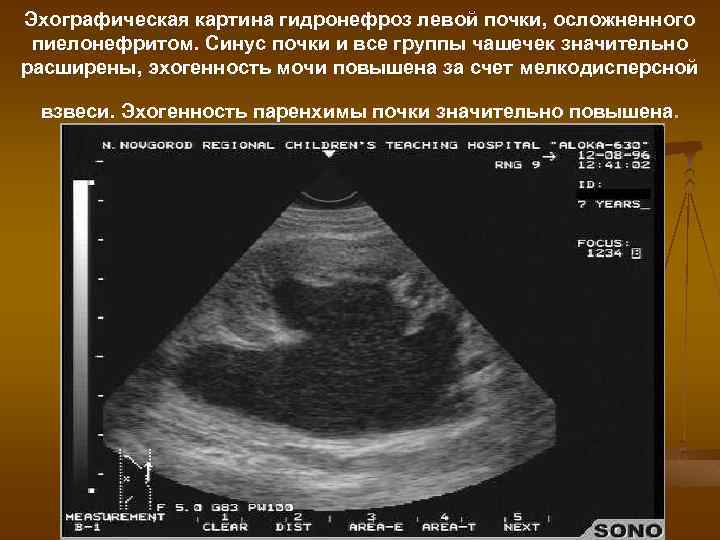

Эхографическая картина гидронефроз левой почки, осложненного пиелонефритом. Синус почки и все группы чашечек значительно расширены, эхогенность мочи повышена за счет мелкодисперсной взвеси. Эхогенность паренхимы почки значительно повышена.